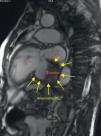

Em virtude de queixas de dispneia e dor retroesternal recorrente, sem alterações eletrocardiográficas de novo e sem elevação dos biomarcadores de necrose miocárdica, o doente fez TAC torácica, que mostrou uma massa hipodensa aparentemente extracardíaca, em relação com a aurícula esquerda. Um segundo ecocardiograma foi então realizado, tendo-se observado uma massa adjacente à aurícula esquerda (39×40mm), cuja continuidade com as cavidades cardíacas era duvidosa (Figuras 1 e 2). Foi então efetuada uma Ressonância Magnética Cardíaca que demonstrou a presença de um volumoso aneurisma ínfero-basal do ventrículo esquerdo, parcialmente preenchido por trombo de grandes dimensões (52×48×32mm). Dada a reduzida espessura da parede deste aneurisma, não foi possível distinguir nela as várias camadas da parede, pelo que não se pôde excluir em definitivo um pseudo-aneurisma com apresentação tardia. Existia algum fluxo entre o trombo e o fundo-de-saco do aneurisma que, no entanto, parecia aderente às paredes do aneurisma nas extremidades superior e inferior (Figuras 3 e 4). Este exame confirmou o compromisso severo da função ventricular esquerda e a insuficiência mitral, por alteração da geometria do ventrículo esquerdo, com marcado repuxamento do folheto posterior.

DiscussãoO diagnóstico entre aneurisma ventricular esquerdo e pseudo-aneurisma é difícil, especialmente quando o aneurisma tem uma localização posterior (3%)2,3. Os verdadeiros aneurismas são definidos como áreas de miocárdio mais fino, discinético, mas constituído por todas as camadas da parede. Por outro lado os pseudo-aneurismas resultam da rotura da parede livre, contida muitas vezes por trombo e pericárdio aderente. Os pseudo-aneurismas do ventrículo esquerdo apresentam assim maior risco de complicações, quando comparados com os aneurismas verdadeiros, sendo a mais grave a rotura espontânea, que resulta geralmente em morte súbita. O diagnóstico diferencial das duas situações é difícil, sendo muitas vezes um diagnóstico cirúrgico, pois têm muitas características comuns4. Um miocárdio fino ou com rotura move-se discineticamente ou não contrai, conduz à ocorrência de insuficiência cardíaca e arritmias ventriculares malignas, podendo estas ocorrer em ambas as patologias5. A deteção da massa adjacente à aurícula esquerda pela TAC e ecocardiografia tornou-se um desafio diagnóstico. A Ressonância Magnética Nuclear confirmou a existência de trombo associado a aneurisma/pseudo-aneurisma. No entanto, a dificuldade de detetar a continuidade do miocárdio, manteve-se com esta técnica. A intervenção cirúrgica, nos casos de aneurisma verdadeiro, visa melhorar a função do ventrículo esquerdo e reverter o remodelling, reduzindo a probabilidade de arritmias malignas, eventos embólicos e assim melhorar a sobrevida dos doentes com esta complicação.